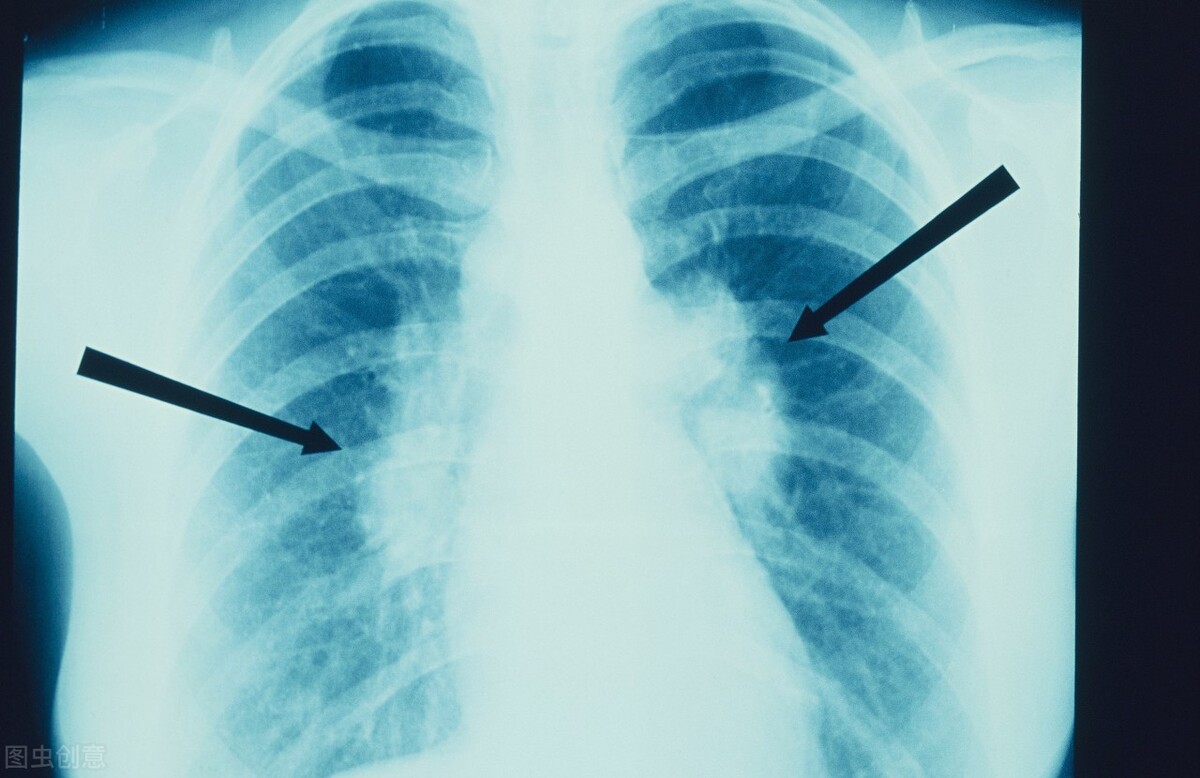

肺结节一般来说属于虚实错杂之症,脏腑内虚为发病基础,治疗上以补益为基本原则,重视培补正气。我曾接诊一位患者,患者因受凉出现咳嗽,咯黄白色黏痰且不易咯出,出现低热盗汗以为是感冒、后来出现烦躁易怒、四肢倦怠、失眠头晕等症。后去医院检查胸部CT显示:肺门淋巴结肿大、肺野可见栗粒状结节。诊断为“肺结节病”并给予激素治疗,效一般。后来患者因担心激素依赖性及毒副作用就想中医治疗,继而找到了我。